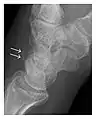

The greater tuberosity of the humerus is also an illustrative location of occult fractures. The osseous injury may follow seizures, glenohumeral dislocation, forced abduction, or direct impaction. They are commonly discovered on MRI in symptomatic patients with suspicion of rotator cuff tear. Coronal images are best suited for detection. They appear as crescentic oblique lines surrounded by a bone marrow edema pattern (Figure 5). The rotator cuff must be inspected since associated ligamentous lesions are common. In the ankle, malleoli and tarsal bones should be checked carefully for any cortical disruptions and radiolucent lines that may reveal a fracture. Awareness of the exact location of the pain will help direct the attention of the interpreter when searching for very subtle signs of fracture (Figure 6).[1]

Figure 6: Subtle anterior talar fracture in a 39-year-old man presenting with ankle pain after a fall. (a) Anteroposterior radiograph shows a subtle oblique radiolucent line through the talus (white arrows). (b) Sagittal CT reformation confirms the presence of an anterior talar fracture with cortical offset (black arrow). Avulsion fractures, which consist of a detached bone fragment resulting from a ligament or tendon pulling away from the bone, may also present with subtle radiographic signs. Tiny osseous fragments near the presumed attachment site of a ligament suggest this diagnosis. Common sites are the lateral tibial plateau (the Segond fracture), the spinal tuberosity of the tibia resulting from anterior cruciate ligament avulsion, and the ischial tuberosity.[1]